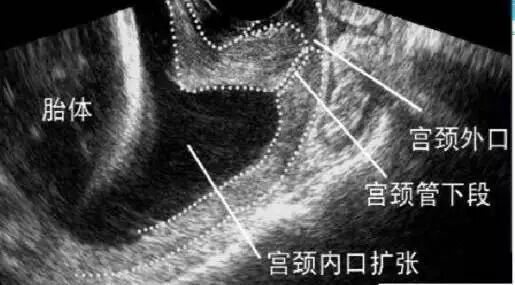

宫颈是子宫的大门,它分为内门、外门和中间的一个通道,承托着子宫。怀孕中期,胎儿逐渐长大、羊水量增多、子宫增大,宫颈负担加重。宫颈机能不全的孕妇,内门相对比较松弛,还没到足月分娩就提前打开了。内门越开越大,最后外门也会打开,宫颈全程开放。有些孕妇虽然宫颈内口(内门)还没开,但宫颈的长度(内外门中间的通道)明显缩短,预示着继续怀孕下去可能发生晚期流产或者早产。

另一个主要的诊断方法是孕期经阴道超声监测宫颈。如果发现宫颈长度小于25mm,宫颈内口呈现”Y”字型、“V”字型、“U”字型漏斗,就要小心了!